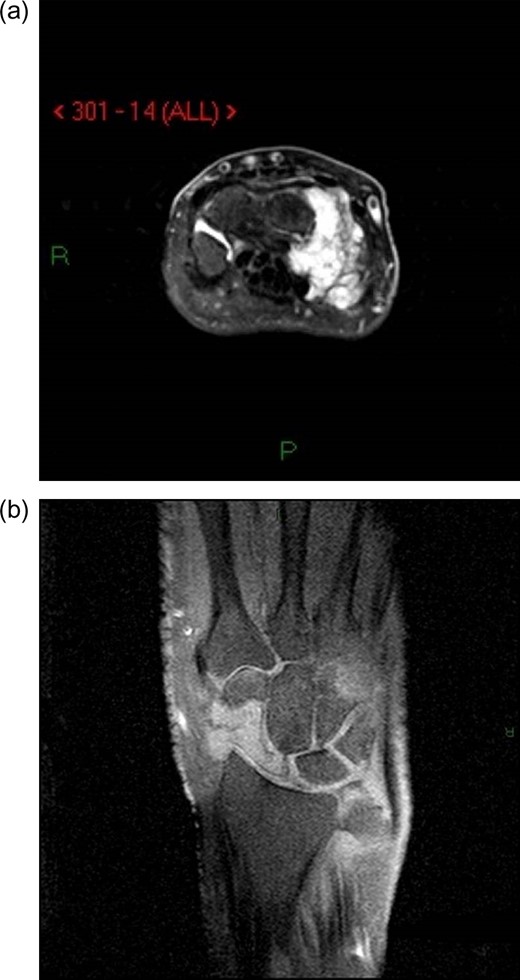

Radiographs of the right hand and wrist revealed a lytic lesion in the scaphoid with nearly complete destruction of the distal pole (Fig. 1a–c). The lateral radiograph also demonstrated some abnormal scalloping of the distal radius articular surface (Fig. 1c). Magnetic resonance imaging (MRI) showed destructive changes of the radial sided carpus (Fig. 2a and b), suggestive of neoplastic or infectious processes, but was inconclusive.

(a) AP image of the wrist showing a destructive lesion within the carpus. (b) Oblique image of the wrist showing a destructive lesion within the carpus. (c) Lateral view of the wrist showing a destructive lesion within the scaphoid. Note the near dissolution of the distal scaphoid and scalloping of the distal radius articular surface.